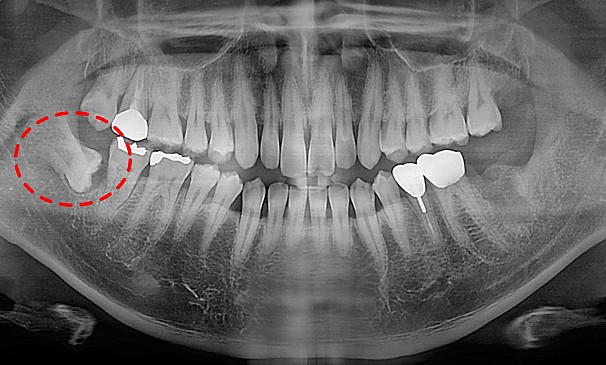

자가치아이식술

김OO님 전후사진 | 치료 기간 : 2주

치료 전

치료 후